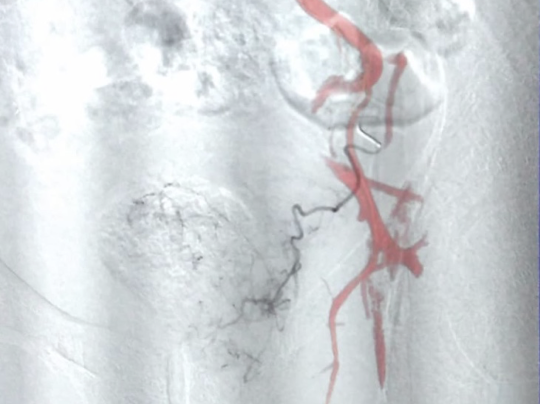

Un cathéter de 1,6 mm est introduit par l'accès artériel et est guidé à l'aide des rayons X jusque dans les artères iliaques internes. Puis un microcathéter de 0,6 mm de diamètre est introduit dans le cathéter dit porteur (système co-axial) jusqu'aux artères prostatiques.

Les artères prostatiques connaissent de nombreuses variantes d'où la difficulté potentielle du geste. Il peut exister une à deux artères par côté (1,4 en moyenne). Le diamètre des artères prostatiques est d'environ 1 mm. L'origine de ces artères est très variable en fonction des patients ce qui rend ce geste difficile. Une acquisition 3D permet de repérer la ou les artères prostatiques et de les cathétériser à l'aide d'une superposition entre l'image 3D et l'image radiographique.

Une fois placé dans l'artère prostatique, on s'assure par des acquisitions 3D de l'absence d'anastomose et donc l'absence de risque d'embolisation hors cible. Puis, on injecte des microparticules (diamètre moyen de 300 à 500 microns) jusqu'à arrêt complet du flux. Ces microparticules peuvent être remplacées ou complétées par l'injection d'un agent liquide (Onyx® ou Glubran®) en fonction de la configuration vasculaire qui ont l'avantage de réaliser une occlusion complète et définitive du vaisseau cible avec une meilleure visualisation à l'injection.